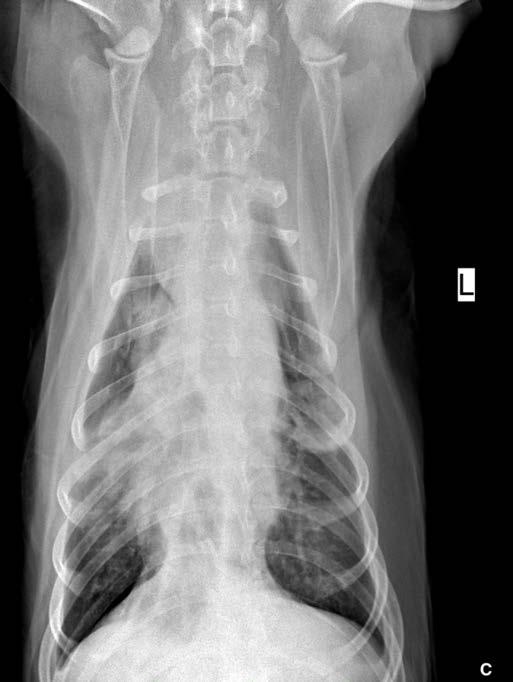

Se realiza ecocardiografía en la cual observamos engrosamiento de la válvula mitral (Fig. 2) y alteración de la estructura de las cámaras cardiacas: ratio atrio izquierdo/aorta 2,25 (Fig. 3), diámetro de ventrículo izquierdo en diástole normalizado (DVIdn) 1,98, patrón de flujo transmitral pseudonormal con velocidad máxima de onda E de 1,7 m/s, tiempo de relajación

isovolumétrica (TRIV) acortado, 30 ms, y regurgitación mitral de hasta 4,6 m/s. En la ecocardiografía se observa también una masa hiperecoica bien definida de hasta 7 x 4,3 cm de diámetro en la base aórtica (Fig. 4) y un acúmulo de derrame pericárdico leve que no permite la pericardiocentesis. Además, se detecta un nódulo hiperecoico redondeado de 1,56 cm de diámetro en la válvula tricúspide (Fig. 5).

Figura 2. Ecocardiografía en corte paraesternal izquierdo eje largo, de 4 cámaras en la que se observa engrosamiento de la válvula mitral (flecha). Figura 3. Ecocardiografía en corte paraesternal derecho eje corto en base de corazón, visualizando ratio atrio izquierdo/aorta aumentado. Figura 4. Ecocardiografía en corte paraesternal izquierdo en base de corazón, en las que se observa la estructura hiperecoica y heterogénea junto a la aorta en un corte de la lesión transversal (A) y otro longitudinal (B). Compatible con neoplasia. A B Figura 5. Ecocardiografía en corte paraesternal izquierdo eje largo, optimizada para válvula tricúspide en la que se observa estructura hiperecoica.

La ecocardiografía es el método de elección para confirmar el diagnóstico de EDVM y estimar la severidad de la regurgitación mitral. Los hallazgos ecocardiográficos incluyen el engrosamiento y/o prolapso de las hojas mitrales junto con la identificación de la regurgitación mediante Doppler. Como se comprobó en el estudio post mortem en nuestro caso, a menudo se observan alteraciones en la válvula tricúspide, pero suelen ser menos marcadas que las de la válvula mitral.2 La ecocardiografía permite adquirir dimensiones del AI en relación con la aorta, o valoración del diámetro del VI en diástole y sístole, muy útiles para estimar el grado de remodelación (agrandamiento) cardíaco.2